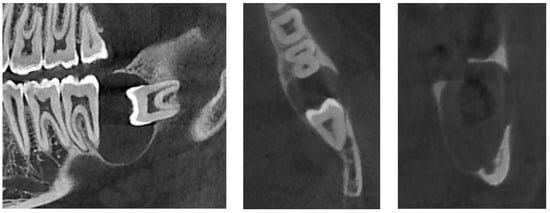

An additional cone-beam computed tomography (CBCT) X-ray examination confirmed the presence of the large pericoronal cystic lesion attached to the cementoenamel junction of tooth #38 (Figure 2). We observed a bone expansion accompanied by slight thinning of the mandibular cortex on the vestibular and lingual sides. The cyst was in contact with the upper wall of the IAC, which was thinned and caudally displaced, but of normal width. This lesion had an approximately 8 mm opening on the mucosal alveolar crest and extended to the distal root of tooth #37 without signs of associated root resorption.

Figure 2.

CBCT X-ray of case #1.

There was also no periosteal reaction, pathological fracture, evident signs of sequestration or sclerosis of the surrounding bone, nor infiltration of the perimandibular soft tissues. Tooth #38 had two roots, and the mesial root came into contact with the lingual wall of the IAC. The radiological appearance evoked a DC. Differential diagnoses included odontogenic keratocyst and unicystic ameloblastoma. The lesion was enucleated in toto together with tooth #38 under local anesthesia. The diagnosis of DC was confirmed by histopathological examination (Figure 3). The patient was followed for four years. At 12 months follow-up, OPG showed satisfactory healing of the enucleation cavity and tooth #37 was still vital (Figure 4). The patient was followed-up for 4 years with no signs of recurrence.